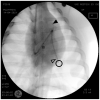

For the non-invasive assessment of pulmonary artery pressure (PAP), surrogates like pulse wave transit time (PWTT) have been proposed. The aim of this study was to invasively validate for which kind of PAP (systolic, mean, or diastolic) PWTT is the best surrogate parameter. To assess both PWTT and PAP in six healthy pigs, two pulmonary artery Mikro-Tip™ catheters were inserted into the pulmonary vasculature at a fixed distance: one in the pulmonary artery trunk, and a second one in a distal segment of the pulmonary artery. PAP was raised using the thromboxane A2 analogue U46619 (TXA) and by hypoxic vasoconstriction. There was a negative linear correlation between PWTT and systolic PAP (r = 0.742), mean PAP (r = 0.712) and diastolic PAP (r = 0.609) under TXA. During hypoxic vasoconstriction, the correlation coefficients for systolic, mean, and diastolic PAP were consistently higher than for TXA-induced pulmonary hypertension (r = 0.809, 0.778 and 0.734, respectively). Estimation of sPAP, mPAP, and dPAP using PWTT is feasible, nevertheless slightly better correlation coefficients were detected for sPAP compared to dPAP. In this study we establish the physiological basis for future methods to obtain PAP by non-invasively measured PWTT.